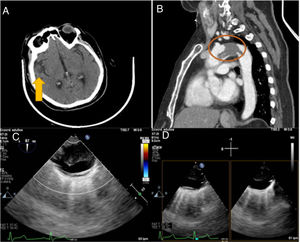

Se le realizó una tomografía axial computarizada (TAC) craneal con hallazgos compatibles de proceso isquémico hiperagudo en el territorio de la arteria cerebral media izquierda (M2 distal) y una TAC de aorta, en la que se apreció un trombo pediculado de 7cm en la aorta torácica con origen en el cayado aórtico (fig. 1). Tras valoración multidisplinar por parte de cirugía cardíaca, neurorradiología intervencionista y neurología, se decidió desestimar la trombectomía mecánica por dificultad técnica y por la urgencia, por posible síndrome aórtico agudo.

A) Tomografía axial craneal: proceso isquémico hiperagudo en territorio de la arteria cerebral media izquierda (M2 distal). B) Angiografía de aorta. Defecto de repleción de 7cm, que se extiende desde el plano tubular de la aorta ascendente hasta el istmo aórtico en una aorta sin clara ateroesclerosis. Este trombo genera estenosis de 18mm en el cayado aórtico entre el origen de la arteria carótida común izquierda y la arteria subclavia izquierda. C) Ecografía transesofágica. Trombo en aorta, que llega a subclavia izquierda y parece ocupar todo el cayado. Espesor máximo de 16mm. D) Ecografía transesofágica (Xplane). Trombo arterial junto con guía flexible a través de subclavia izquierda.

Se le indujo una anestesia general con secuencia rápida, con monitorización invasiva de la presión arterial de ambas arterias radiales, presión venosa central, oximetría cerebral no invasiva, bisprectal index y ecografía transesofágica (ETE) para localización del trombo en cayado aórtico (fig. 1); se usó guía flexible para posible despliegue de prótesis híbrida. Previa heparinización del paciente con 3mg/kg, disección y canulación directa de la arteria axilar derecha, se le realizó esternotomía media, canulación de aurícula derecha, seno coronario y disección de troncos supraaórticos con administración de cardioplejía hemática por vía retrógrada. Tras parada cardiocirculatoria con perfusión unilateral de 37 min con hipotermia moderada (24?°C) se efectuó aortotomía longitudinal en el arco aórtico y en la aorta ascendente distal.